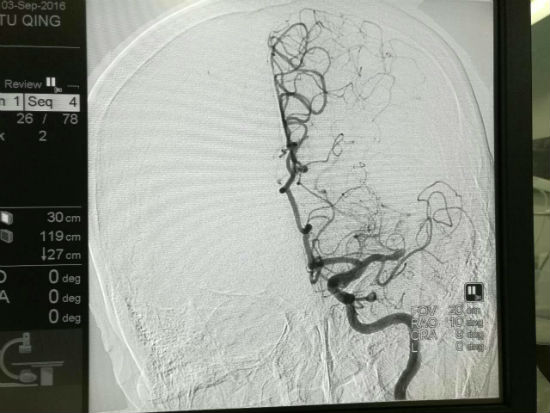

一系列術(shù)前準(zhǔn)備完成后,符鵬程主任帶領(lǐng)其團(tuán)隊(duì)迅速進(jìn)入醫(yī)院介入手術(shù)室,從患者的股動(dòng)脈進(jìn)入,20分鐘完成造影,接著應(yīng)用支架取栓器,取出了數(shù)個(gè)血栓,使患者血液得以流通。

手術(shù)前

手術(shù)后

經(jīng)過(guò)半小時(shí)的搶救,患者終于轉(zhuǎn)危為安,復(fù)查造影顯示閉塞大腦中動(dòng)脈完全開(kāi)通,胡某右側(cè)肢體當(dāng)時(shí)便可以活動(dòng)。術(shù)后第二天,胡某右側(cè)肢體活動(dòng)和言語(yǔ)功能已完全恢復(fù)正常,目前其生命體征平穩(wěn)。